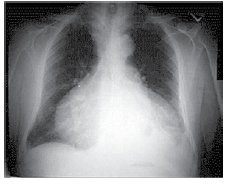

Mulher de 49 anos é internada devido dispneia, febre e dor torácica à esquerda iniciados há 3 dias. Pressão arterial: 110 x 60 mmHg, pulso: 115 bpm; temperatura: 38,3 ºC, frequência respiratória: 26 ipm e saturação arterial de oxigênio: 85%. Radiografia realizada é ilustrada a seguir.

Enunciado 3309351-1

Nesse momento, é correto afirmar: